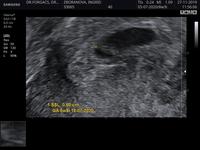

Gynekologická je fakt koza, ako to môže také nervy robiť. Že vak je moc veľký🤦♀️Rovnomerný je a srdce bije, verím, že je všetko v poriadku.

@v_ero_ni_ka nie len som otehotnela zázrakom ale nepozdáva sa mu bože neviem ako sa to po sk vola ale ten kruh pri babu že je veľký

@inka791 dr. mysli plodovy vak ci zltkovy z kt.babo berie ziviny? Ako myslim, ze uz fakt nevie co si vymysliet, zbytocne stresuje a to je to najhorsie.babo rastie, srdiecko bije, ine neries.. a ze sa mas pripravit?? Ako keby sa nedajboze nieco stane tak ta to zasiahne tak ci tak, na to sa neda pripravit..tak mu nabuduce povedz nech si rady tohto typu necha pre seba a az ked bude realne nieco zle nech povie..uzivaj si tehotenstvo a no stress 🍀🍀🍀

@limetka713 ak som ho dobre pochopila tak zltkovy vak myslel